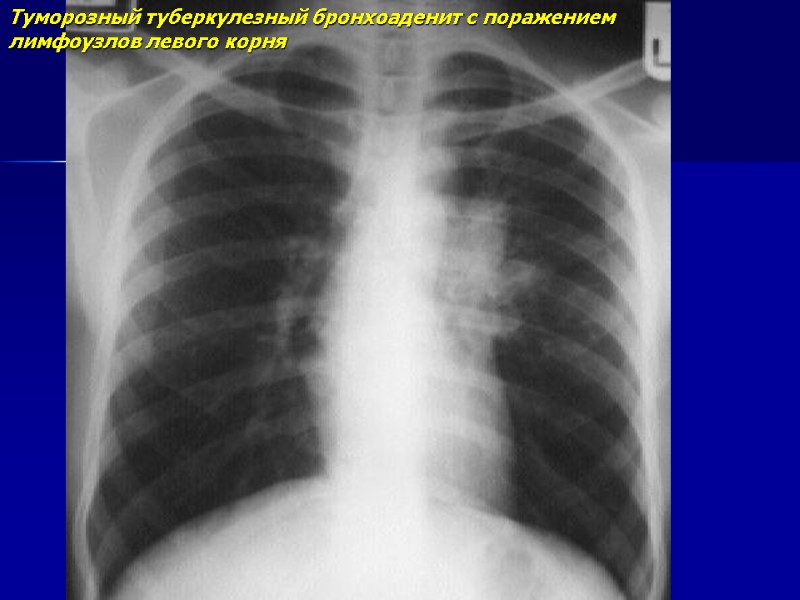

Туморозный туберкулезный бронхоаденит с поражением лимфоузлов левого корня